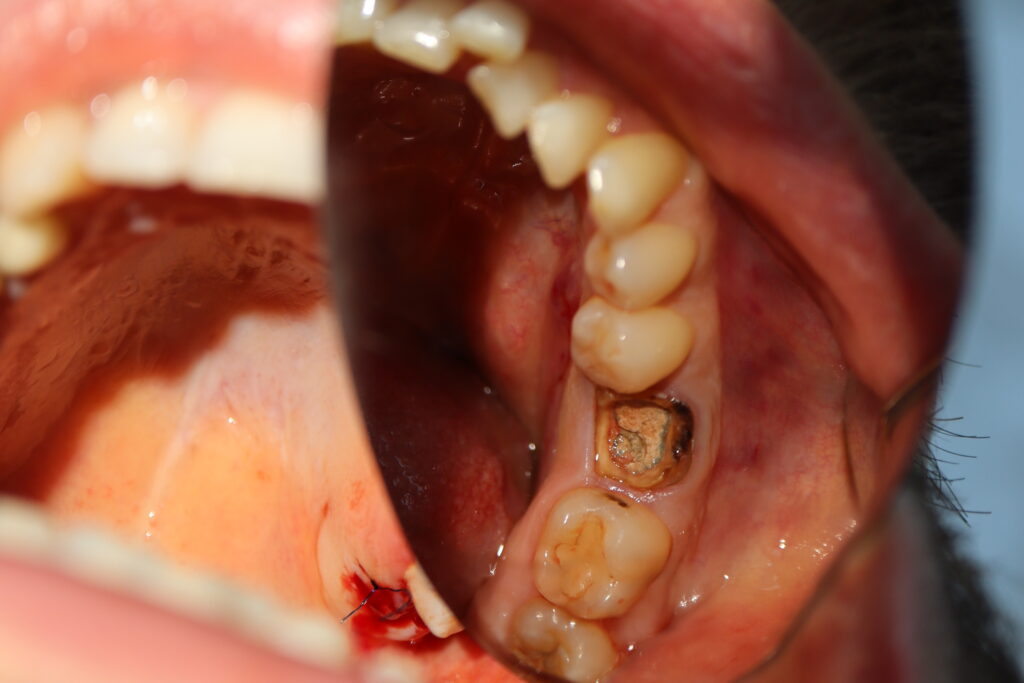

пациент до имплантации